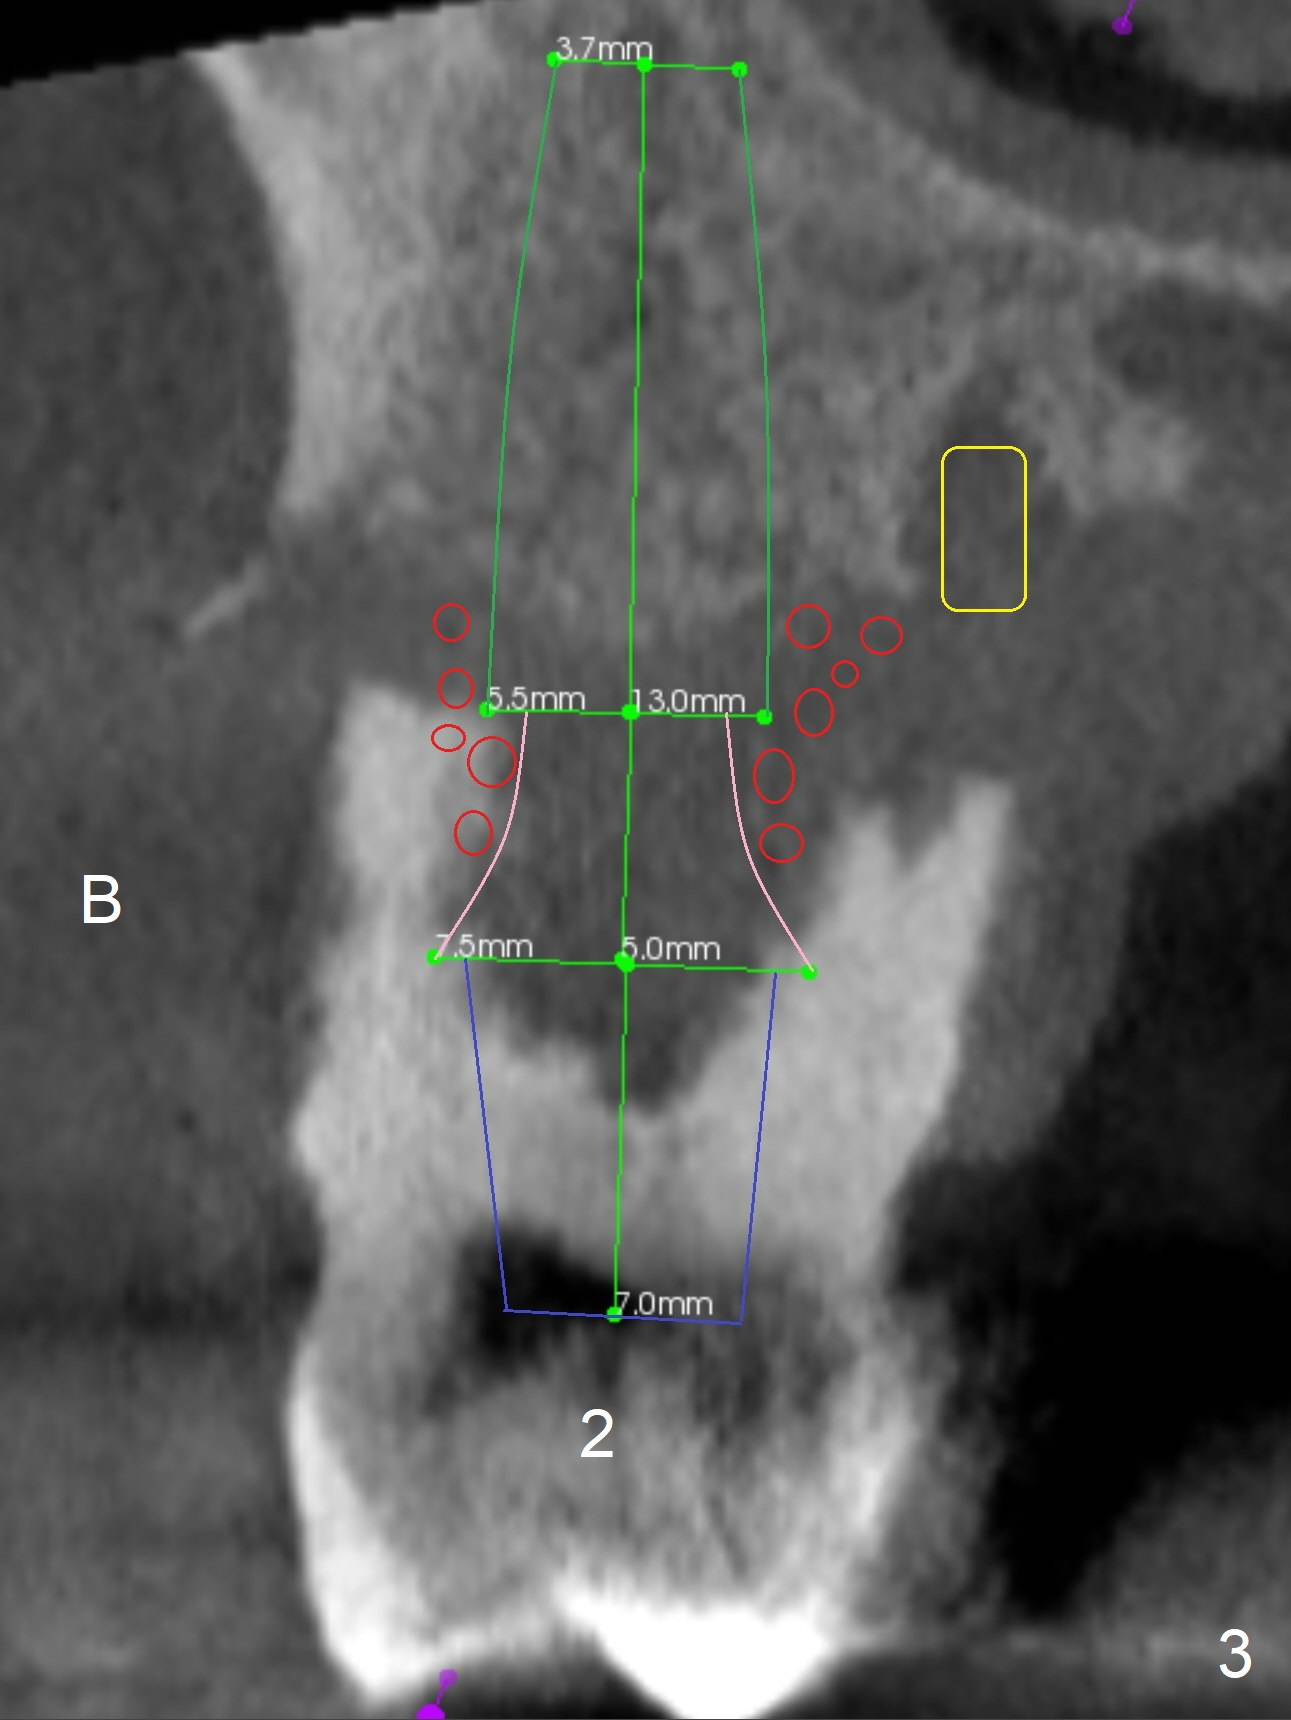

Extract #2 or remove #3-5 FPD first whichever is looser. Use the other as reference guide. Place Osteogen plug in the palatal socket of #2 ad 3 (Fig.3,4 yellow box) and allograft around the implants (red circles).